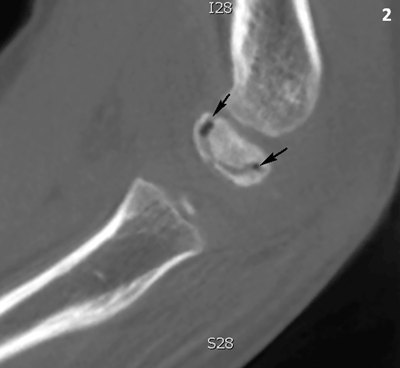

Figure 2

Cone beam CT of the right elbow, sagittal reformatted image. The capitellum has an increased density. There is a subchondral crescent-shaped vacuum phenomenon (black arrows).